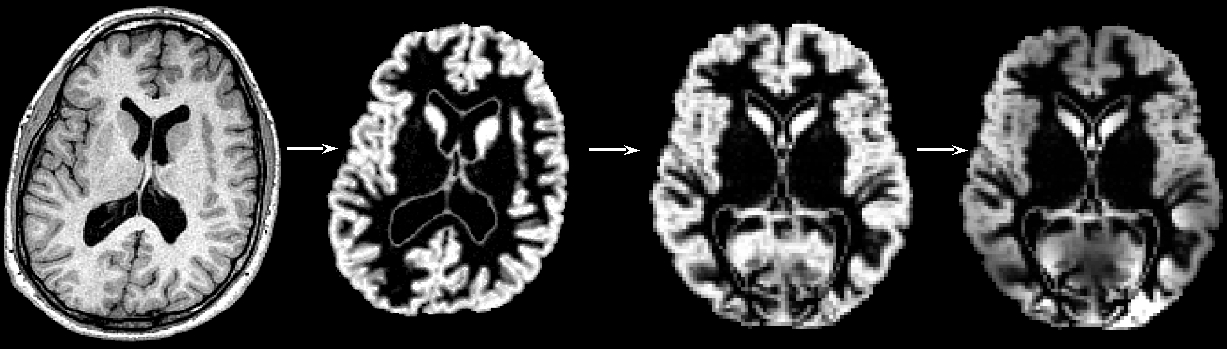

"Structural data was analysed with FSL-VBM (Douaud et al., 2007, http://fsl.fmrib.ox.ac.uk/fsl/fslwiki/FSLVBM), an optimised VBM protocol (Good et al., 2001) carried out with FSL tools (Smith et al., 2004). First, structural images were brain-extracted and grey matter-segmented before being registered to the MNI 152 standard space using non-linear registration (Andersson et al., 2007). The resulting images were averaged and flipped along the x-axis to create a left-right symmetric, study-specific grey matter template. Second, all native grey matter images were non-linearly registered to this study-specific template and "modulated" to correct for local expansion (or contraction) due to the non-linear component of the spatial transformation. The modulated grey matter images were then smoothed with an isotropic Gaussian kernel with a sigma of ?? mm. Finally, voxelwise GLM was applied using permutation-based non-parametric testing, correcting for multiple comparisons across space."